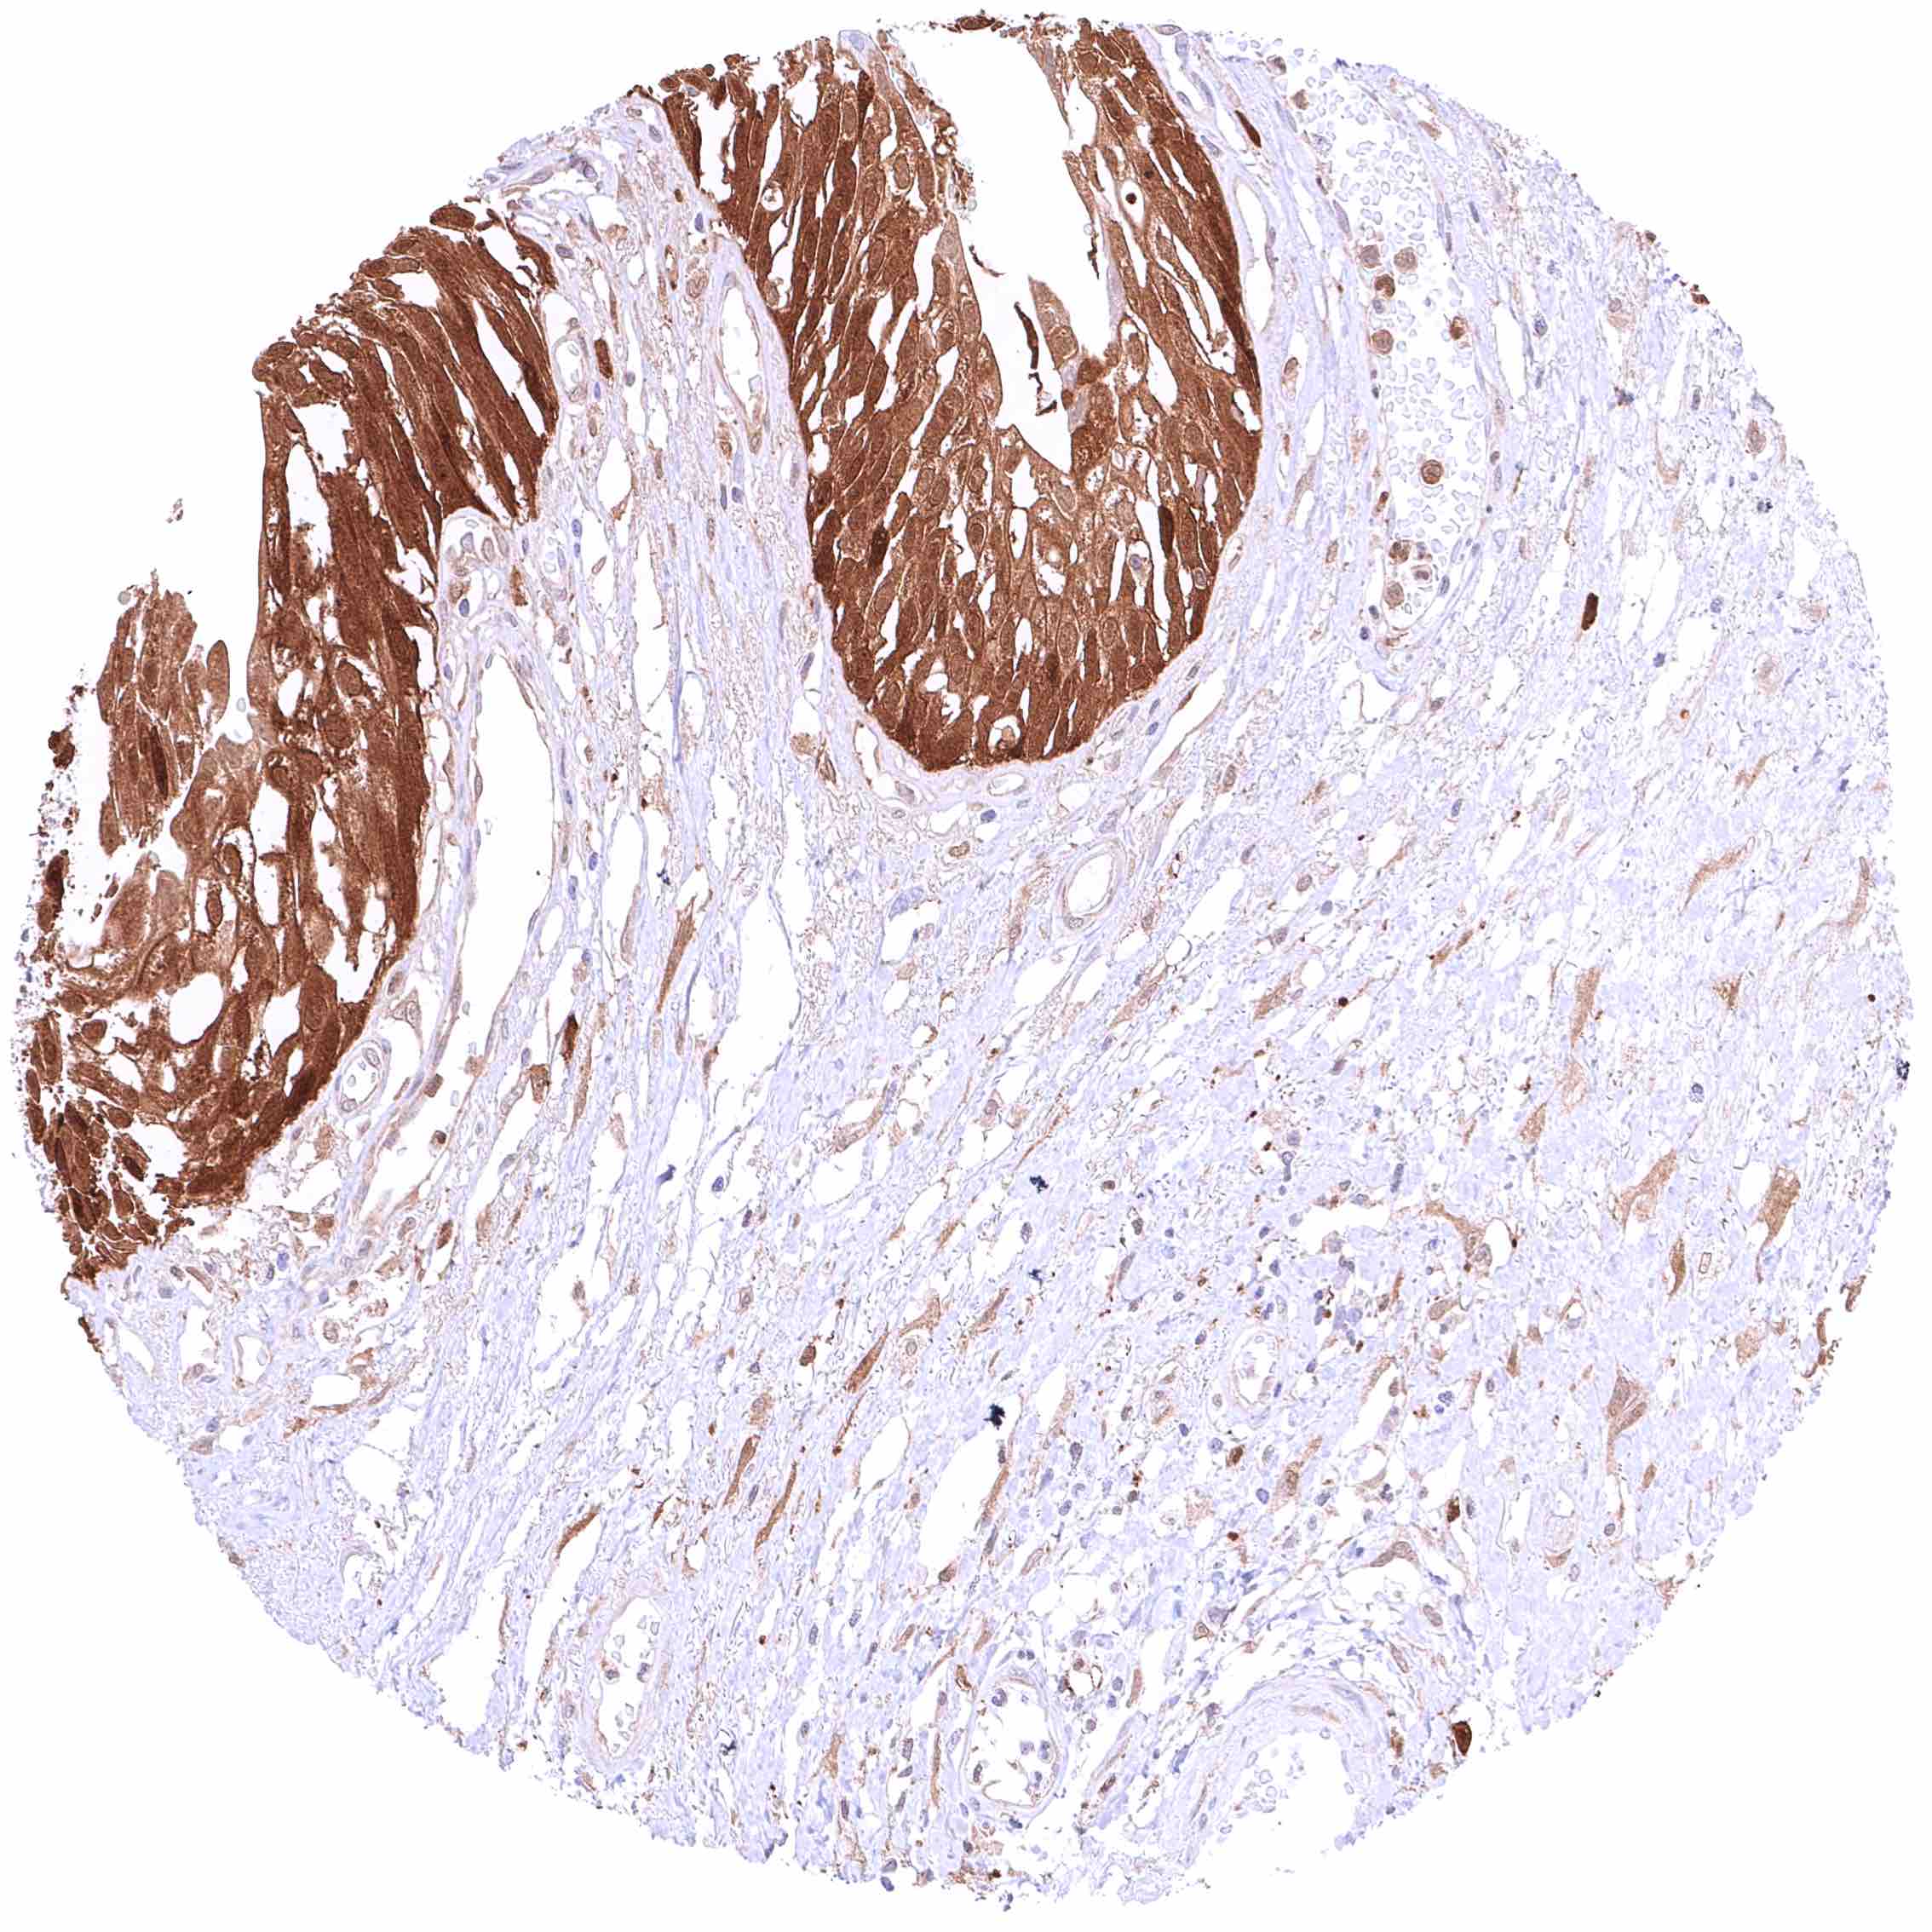

Heart muscle – Most GSTP1 staining occurs around small capillaries while the muscle cells are GSTP1 negative.